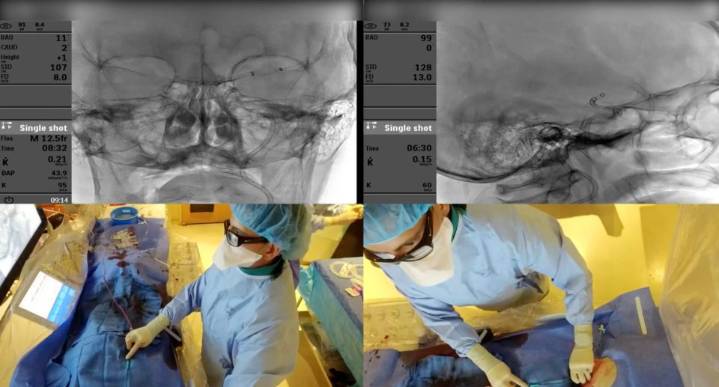

While Memorial Neuroscience Institute (MNI) physicians save lives in South Florida using the latest neurointerventional procedures for brain aneurysms and strokes, they are also sharing clinical and technical expertise with doctors across the globe.

Memorial is one of only three programs in the U.S., and the only one in Florida, selected by the Society of Vascular and Interventional Neurology (SVIN) Mission Thrombectomy initiative to participate in its virtual fellowship for physicians in lower income countries. MNI was chosen for its excellent outcomes, rapid treatment workflow, and care coordination with Emergency Medical Services (EMS) in the community.